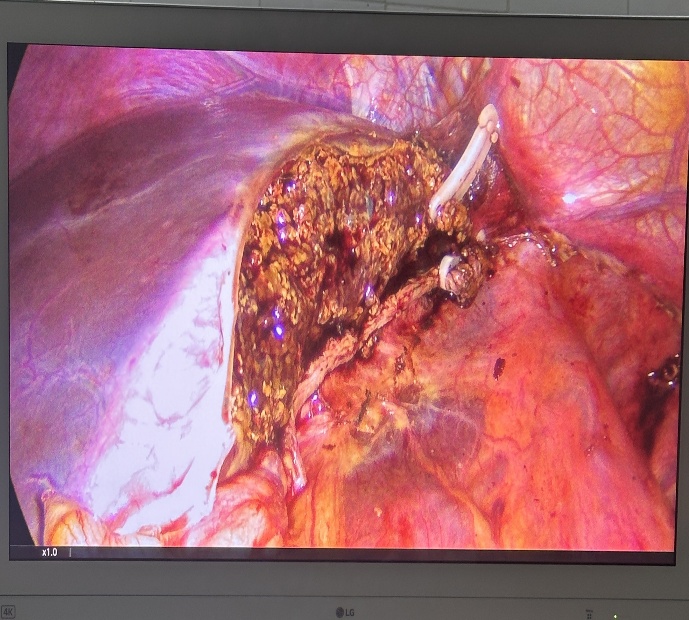

Bệnh nhân nữ 67 tuổi xuất hiện đau hạ sườn phải từng đợt nhiều năm, Mỗi lần đau thường kèm theo sốt, vàng da. BN đã đi khám ở tuyến trên được chẩn đoán tắc mật do sỏi ống mật chủ và sỏi trên gan. BN được chỉ phẫu thuật và quyết định mổ tại BVĐK Hải Dương. Chúng tôi sau khi xem xét hồ sơ bệnh án đã quyết định thực hiện phẫu thuật nội soi tán sỏi OMC và sỏi trên gan kèm tán sỏi Laser. Ca mổ đã diễn ra vô cùng thuận lợi. Sau 2 tiếng ca mổ đã hoàn thành. Sỏi trên gan và sỏi OMC được tán nhỏ và lấy qua nội soi. Sau 10 ngày điều trị hậu phẫu bệnh nhân đã được ra viện.

Hình ảnh sỏi và BN sau mổ với vết mổ rất nhỏ